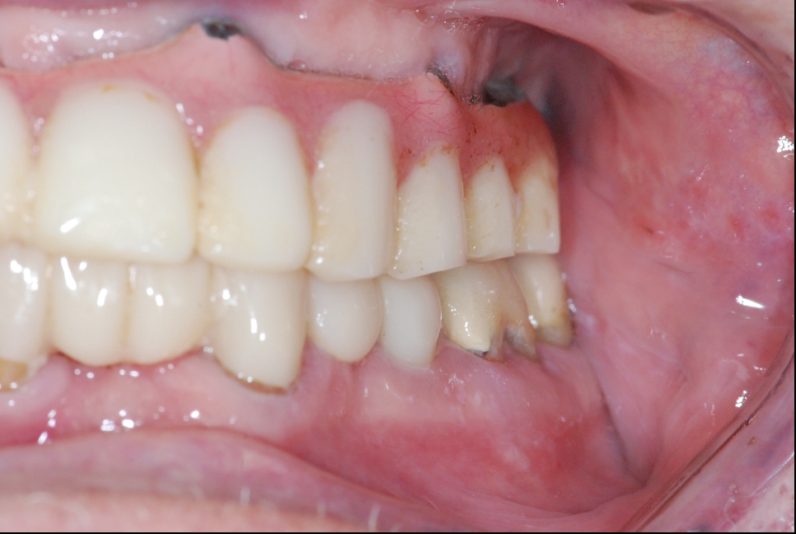

Hey, I will be removing this hybrid denture for replacement. I am having a difficult time locating the access screws for removal. Can anyone please help me find them? Implants are placed at site 3,5,7,9,12,13,15. Thank you for your help!

Use air and really dry the acrylic but you can see the outline of the access on the occlusal of 5,6. I would block enough time and just go slow. Best part is since the prosthesis is plastic it’s easily repairable. U got this.